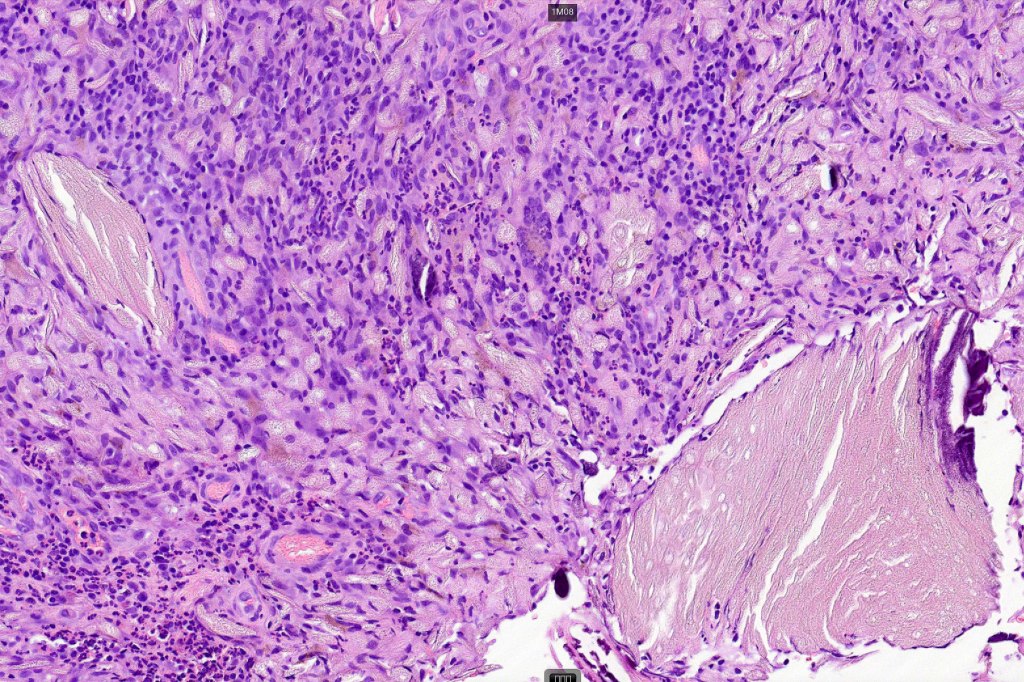

•Basophilic small cells which transition towards supramatricial (orange staining) and ultimately ghost cells with intensely eosinophilic cytoplasm

•Intense mitotic activity may be seen in early lesions (this should not be interpreted as implying malignant potential)

•No abnormal mitoses or pleomorphism

•Foreign body reaction